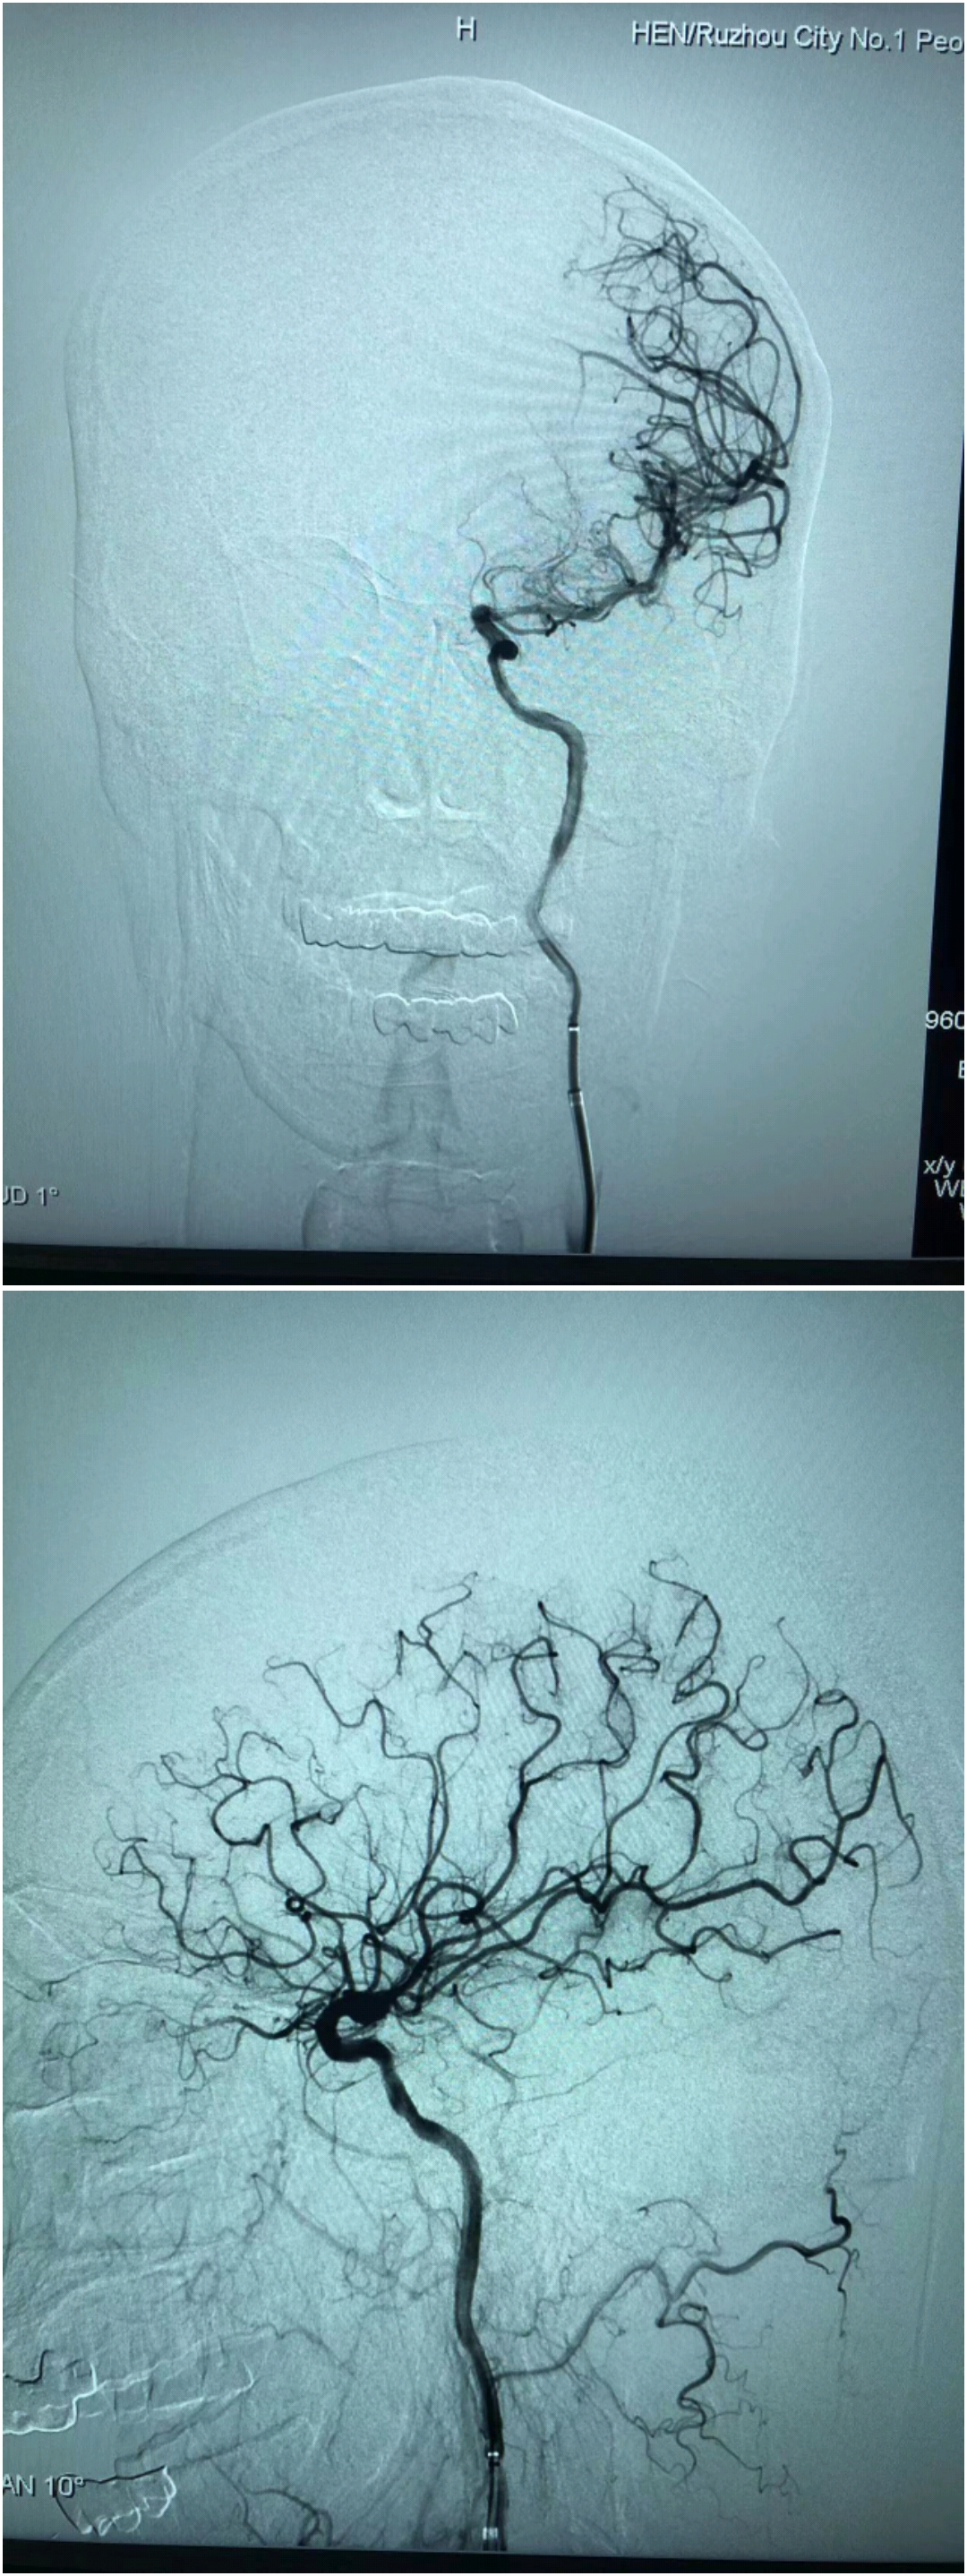

造影:左侧大脑中动脉闭塞,左侧椎动脉闭塞。

术后造影,血流通畅,TICI分级3级。

1.正常可以用取栓支架拉一把,但患者醒后卒中,无房颤病史,梗死位于基底节,皮层部分幸免,考虑有代偿,推测为ICAS闭塞,闭塞近段闭塞形态,以及远端微导管造影,更加确定ICAS。所以没有拉栓,而采用直接球囊扩张。